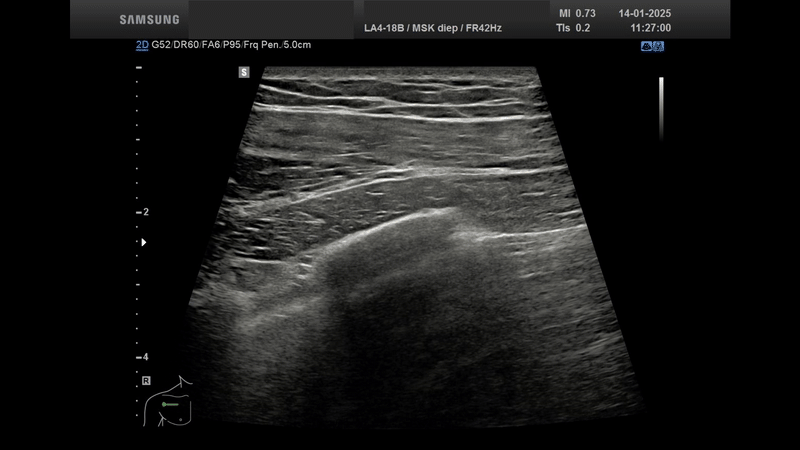

De afgelopen maanden heb ik met veel plezier verpleegkundigen van het dialysecentrum opgeleid in het gebruik van POCUS – Point Of Care UltraSound. Met behulp van een compact en mobiel echotoestel leren zij klinisch snel en doelgericht te handelen, bijvoorbeeld bij een vermoeden van overvulling of bij het beoordelen van de longen.

De training bestond uit drie compacte, praktijkgerichte middagen waarin we stapsgewijs toewerkten naar zelfverzekerd echografisch handelen aan het bed.

• Module 1 richtte zich op echografische techniek en de basisprincipes van beeldvorming.

• Module 2 behandelde de thorax en het abdomen met aandacht voor relevante pathologie.

• Module 3 stond in het teken van herkenbare casuïstiek uit de eigen praktijk, met ruimte voor toepassing en verdieping.

Elke sessie werd ondersteund met live demo’s en ruime hands-on training, zodat theorie direct gekoppeld werd aan praktijk.

Wat deze reeks bijzonder maakte? De samenwerking met professionals uit een totaal ander vakgebied, die met een frisse blik naar echografie kijken. Het bevestigt wat ik in de praktijk steeds vaker zie: echografie ontwikkelt zich razendsnel tot een onmisbaar hulpmiddel – niet alleen binnen, maar juist ook buiten de muren van het ziekenhuis.